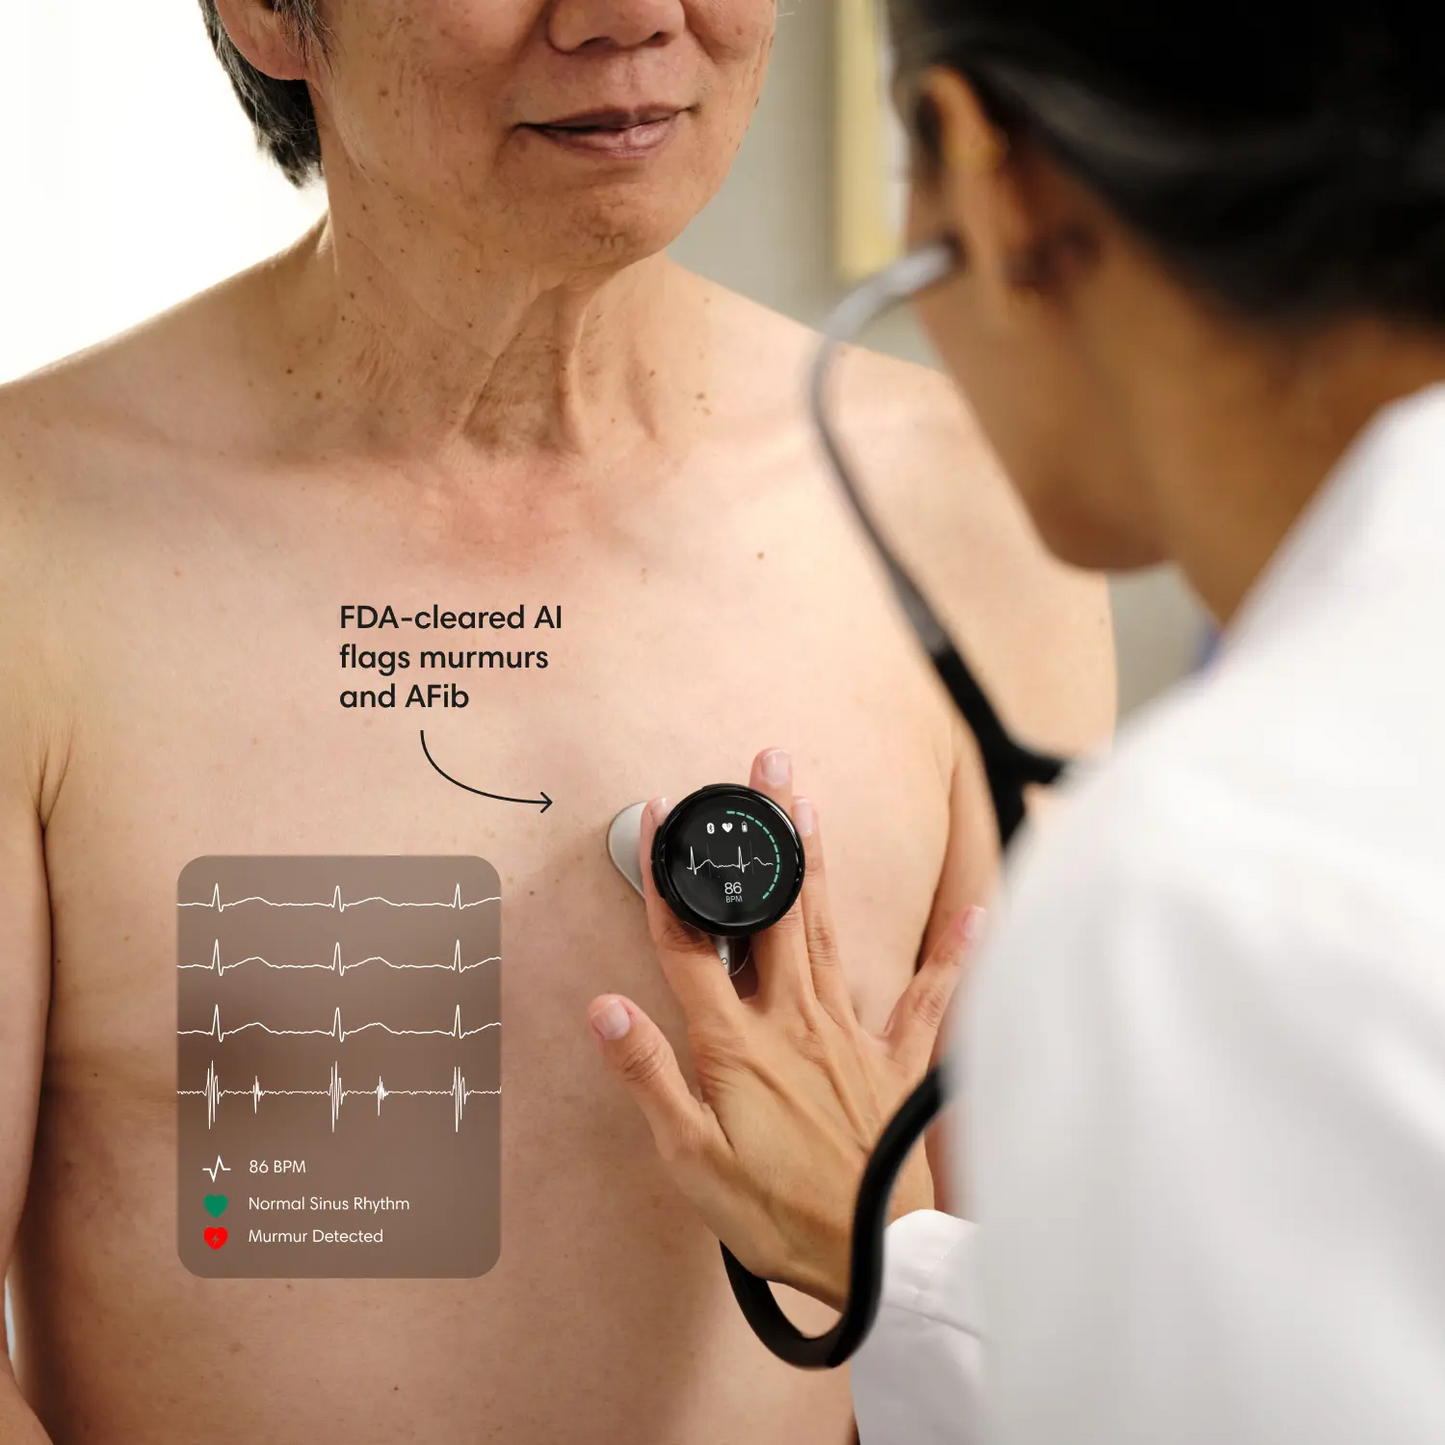

Enhance expertise with AI.

Eko’s FDA-cleared AI flags murmurs and other abnormalities in seconds, leading to earlier heart and lung disease detection and better patient care.

Eko analysis software, or Eko AI, is FDA-cleared software that includes screening algorithms to assist clinicians in detecting suspected abnormalities.

When the Eko App is paired with a compatible digital stethoscope, Eko AI automatically checks for murmurs and/or AFib. To receive AI results, you must take a recording with the stethoscope or the Eko App. (The CORE 500™ Digital Stethoscope is required for AFib detection.)

The Eko App summarizes any findings, including potential murmurs, AFib, or other abnormalities detected. These findings aren’t a diagnosis, but are intended to aid the clinician in reaching a diagnosis accurately, quickly, and confidently.